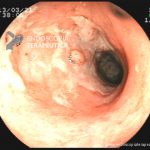

- Doença de Crohn em remissão – cicatriz